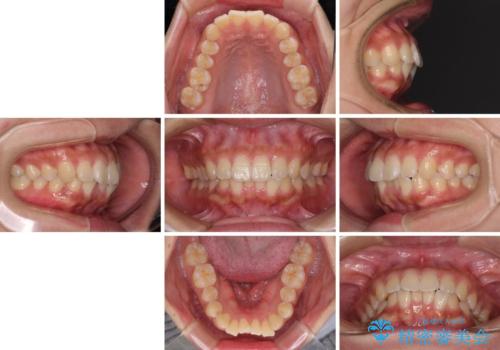

くちばしのような前歯 抜歯矯正で口を閉じやすく

- 前歯の突出感を気にして来院された患者様です。

咬合力が非常に強く、咬合力で前歯が前方に押し広げられており、上下唇に閉じにくさが認められました。

上下左右の第一小臼歯4本を抜歯し、ワイヤー装置にて矯正治療を行うこととしました。

強い咬合力により前歯の隙間がなかなか閉じられず、治療期間は長いものとなりましたが、横顔の印象が大きく変わるほど口元の印象を改善することができました。